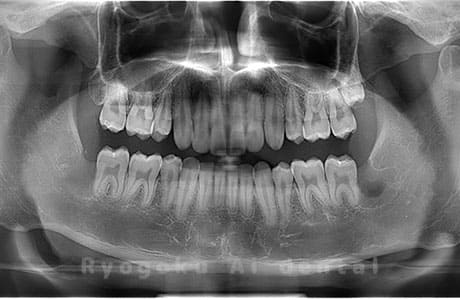

Case02

- 原因

- 下顎の水平埋伏智歯

- 治療内容

- 下顎の水平埋伏智歯を抜歯

<リスク・副作用>

手術後は痛み、腫れ、痺れなどの副作用が生じる場合があります。